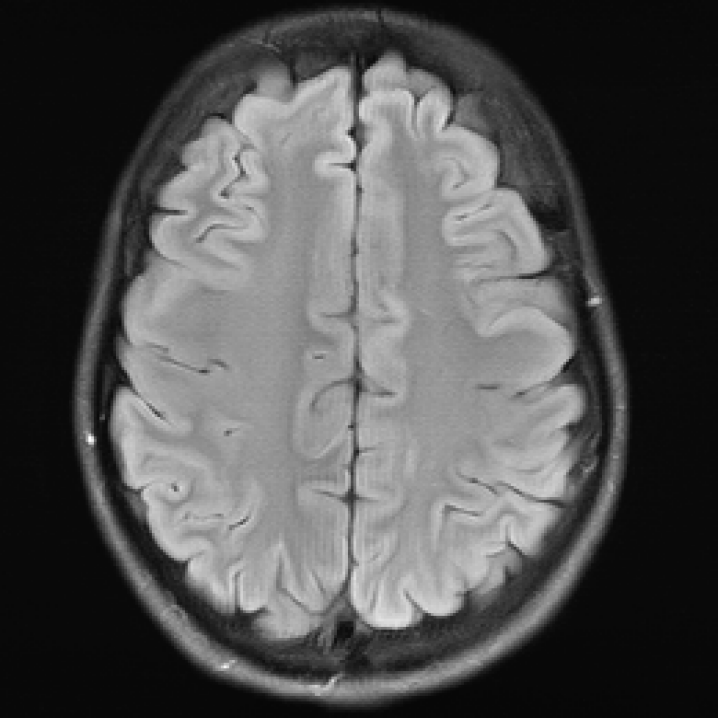

3.2.2 Example 1: Scan acceleration

For this example the data is obtained from the publicly available fastMRI brain dataset (citep \@BBN(Zbontar et al., 2019)), which consists in total of 6405640564056405 T1, T2 and FLAIR 3D k-space volumes. The fastMRI challenge series provided MRI datasets to foster the development of accelerated reconstruction algorithms. The series consists of a knee MRI dataset and challenge in 2019 (citep \@BBN(Knoll et al., 2020)), of a brain dataset and challenge in 2020 (citep \@BBN(Muckley et al., 2021b)), and of a prostate dataset in 2023 (citep \@BBN(Tibrewala et al., 2023)). The winners of the challenges were selected by the comparison of the provided reference images, created by the rSOS of the fully sampled data, to the image outputs of the proposed method via the SSIM and the highest ranked results were submitted to receive experts’ opinion.

We show here images obtained from two machine learning reconstruction algorithms that took part in the fastMRI multi-coil brain dataset challenge in 2020, namely the end-to-end variational network E2E-VarNet (citep \@BBN(Sriram et al., 2020)) and XPDNet (citep \@BBN(Ramzi et al., 2021)). XPDNet was among the top three submissions of the challenge and both algorithms perform very well on the corresponding public leaderboard (citep \@BBN(NYU Langone Health, )), that allows comparison of algorithms submitted after the challenge deadline. The authors of the XPDNet Algorithm provided two distinct models for different acceleration factors. Here, we employ the neural network provided for acceleration factor 4. The reconstructions in Figure 5 were obtained by the application of E2E-VarNet, Figure 5 (b)(c)(e)(f), and XPDNet, Figure 5 (a)(d), to sub-sampled data with random masks (acceleration factor between 1 to 5) in the frequency domain.

Refer to caption

(a) (27.8, 0.78, 0.14)

(b) (29.6, 0.85, 0.14)

(c) (32.3, 0.92, 0.04)

(d) (29.5, 0.84, 0.12)

(e) (29.6, 0.86, 0.12)

(f) (33.0, 0.94, 0.04)

Figure 5: Reconstruction outputs of accelerated FLAIR MRI data from the algorithms Xpdnet(a)(d) and E2varnet (b)(c)(e)(f). The bottom images (d)-(f) are judged by PSNR/SSIM/LPIPS as better reconstructions than the respective image above them (a)-(c), although they contain stronger blur and contain more ringing artifacts.

FR-IQA mismatch

We can see in Figure 5 that the visual quality of the obtained images does not correspond to the numbers provided by PSNR/SSIM/LPIPS, since the images with better numbers (bottom row) suffer from information loss due to blur and ringing. This is not surprising as some challenges with SSIM as a performance metric have already been discussed and shown in the official results paper of the fastMRI challenge (citep \@BBN(Muckley et al., 2021a)). Here, we complement with examples where the visual results also ask for a different judgement in a non local manner. Curiously, the degraded images (e) (f) do hold quite higher numbers in comparison to (a) which is nearly noise-free.